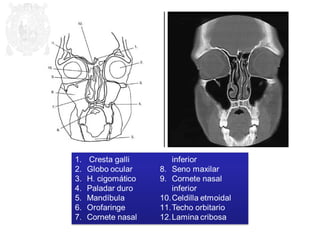

1. Cresta frontal

2. H. frontal

3. Sustancia blanca

4. Cisura o surco

5. Hemisferio parietal

6. Haz cerebral del cerebro